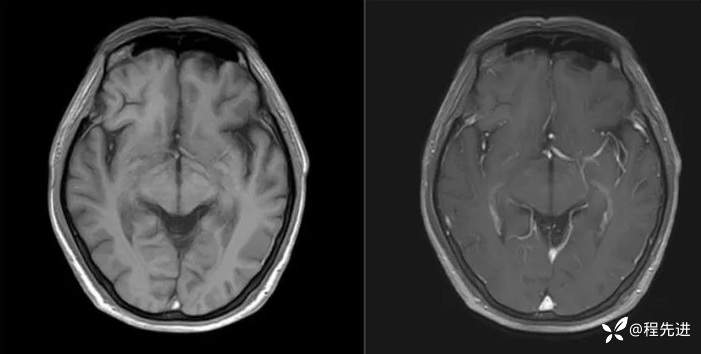

T1、T1增强: